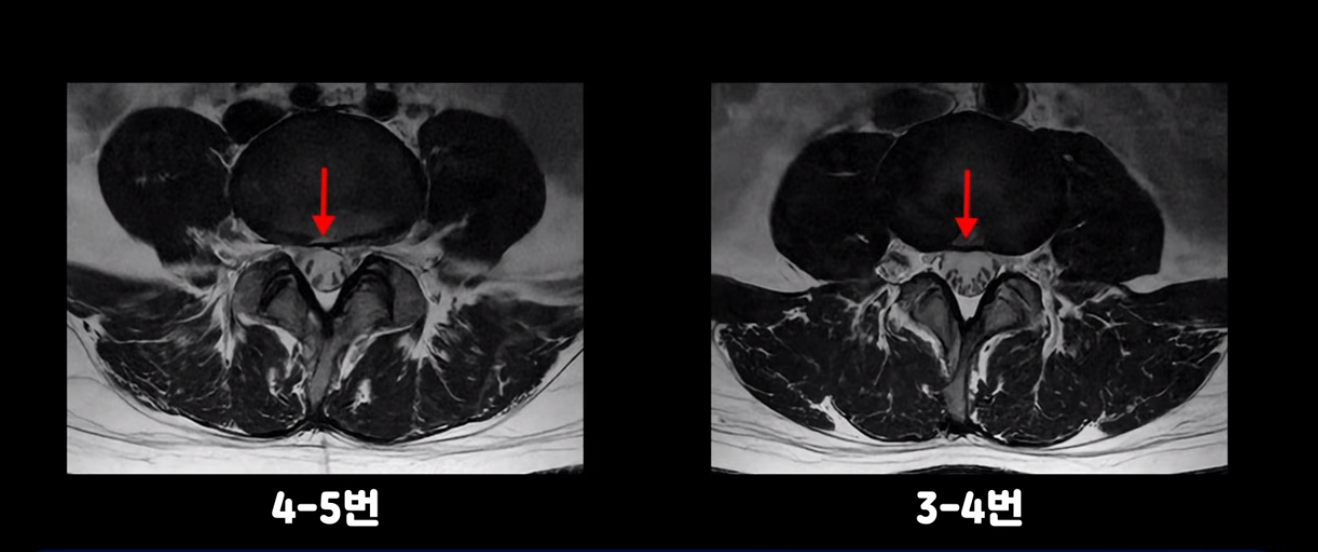

4번 5번과 3번 4번 마디도 디스크가 중앙으로 살짝 밀려나와있지만 최근에 섬유륜이 찢어진 것도 아니고, 신경 다발을 누를 정도로 심하게 밀려나와 있는 것도 전혀 아닙니다.

양쪽 신경 가지가 빠져나가는 추간공도 충분히 넓어서 신경학적 방사통을 일으킬 여지가 없습니다.